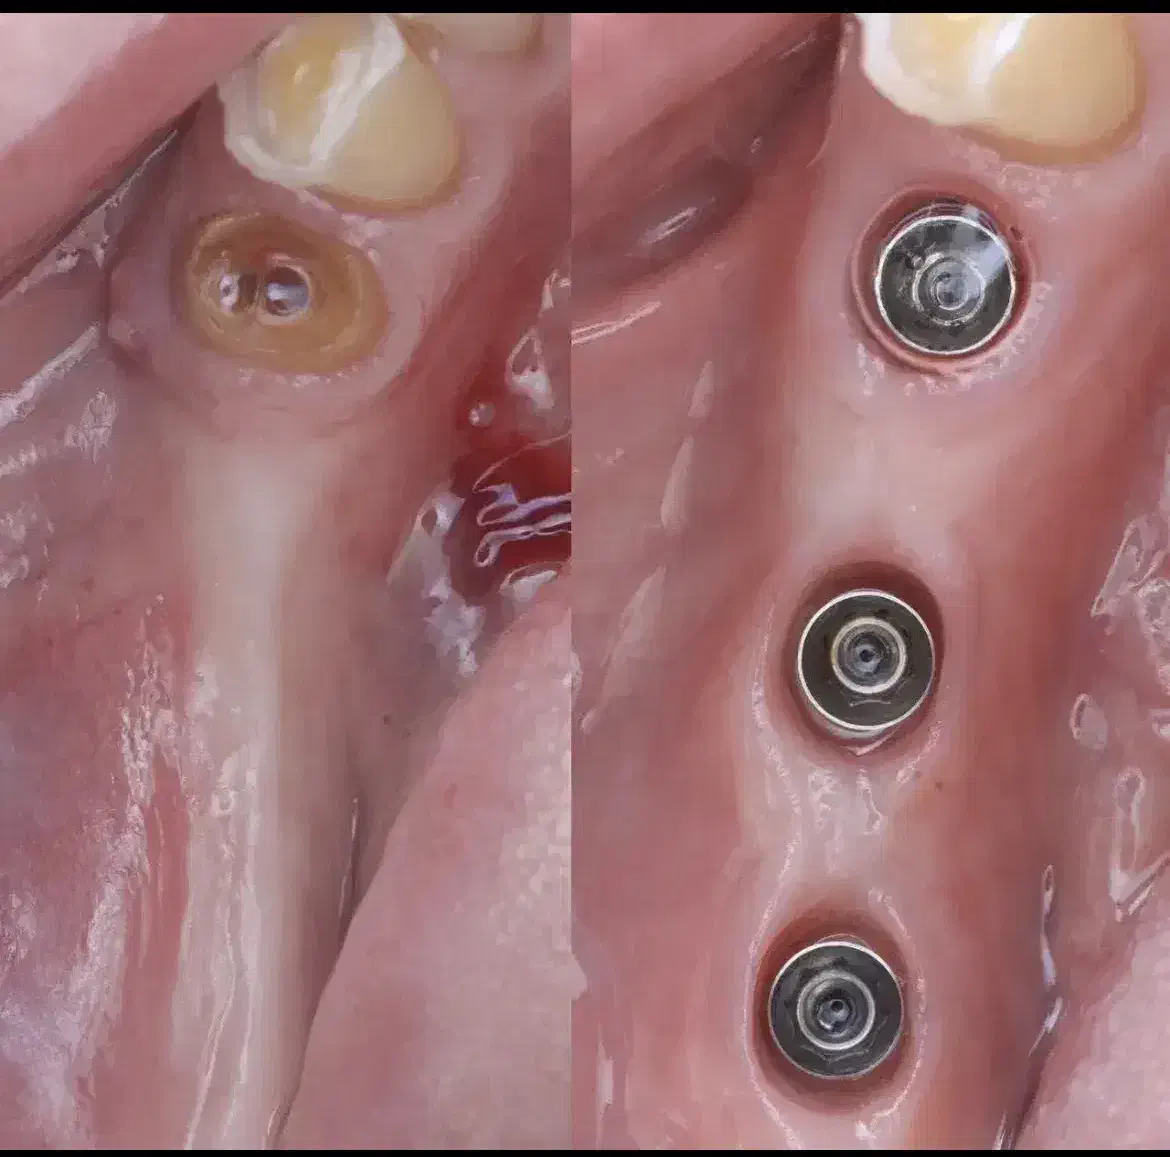

⚜️مطب دندانپزشکی ما، با بهرهگیری از دانش روز و تکنولوژیهای پیشرفته ، خدمات تخصصی دندانپزشکی و ایمپلنت را با بالاترین استانداردهای کیفی ارائه میدهد خدمات و امکانات ویژه: ویزیت و مشاوره اولیه رایگان شرایط پرداخت اقساطی بلند مدت فضای پارک اختصاصی و دسترسی آسان محیطی کاملاً بهداشتی و استریل جراحی ایمپلنت با حداقل تهاجم : استفاده از تکنیکهای جراحی پیشرفته برای کاهش درد، تورم و خونریزی بعد از عمل و تسریع دوره نقاهت بازسازی استخوان :استفاده از تکنیکهای پیشرفته بازسازی استخوان برای افزایش حجم استخوان فک و ایجاد شرایط مناسب برای قرارگیری ایمپلنت در بیمارانی که دچار تحلیل استخوان شدهاند ✅در مورد شرایط پرداخت اصلا نگران هزینه هاتون نباشید باهر توان مالی که باشید باهاتون راه میایم جهت کسب اطلاعات بیشتر و تعیین وقت مشاوره تماس بگیرید یا فامیلی و شماره تماس خودتون رو از چت دیوار برامون بفرستید باهاتون تماس میگیریم